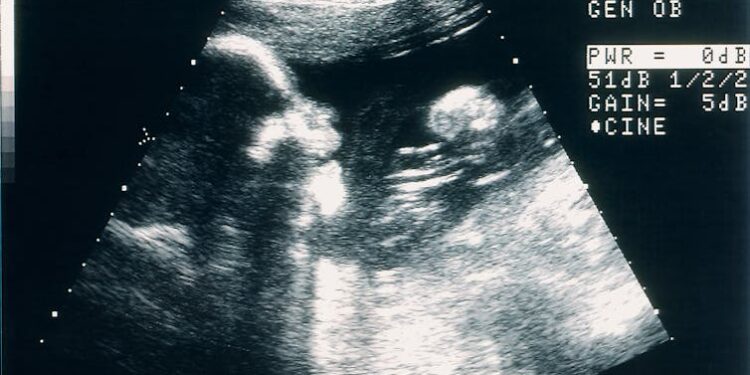

For centuries, Catholic dogma and Western legal precedent have mandated immediate cesarean section when a pregnant woman died after quickening, the point when fetal movement becomes discernible. But technological advances now make it possible sometimes for a fetus to continue gestating in place when the mother is brain-dead, or “dead by neurological criteria”– a widely accepted definition of death that first emerged in the 1950s.

The first brain death during pregnancy in which the fetus was delivered after time on life support, more accurately called organ support, occurred in 1981. The process is extraordinarily intensive and invasive, because the loss of brain function impedes many physiological processes. Health teams, sometimes numbering in the hundreds, must stabilize the bodies of “functionally decapitated” pregnant women to buy more time for fetal development. This requires vital organ support, ventilation, nutritional supplements, antibiotics and constant monitoring. Outcomes are highly uncertain.

Smith’s 112-day stint on organ support ranks third in length for a postmortem pregnancy, with the longest being 123 days. Hers is also the earliest ever gestational age from which the procedure has been attempted. Because time on organ support can vary widely, and because there is no established minimum fetal age considered too early to intervene, a fetus could theoretically be deemed viable at any point in pregnancy.